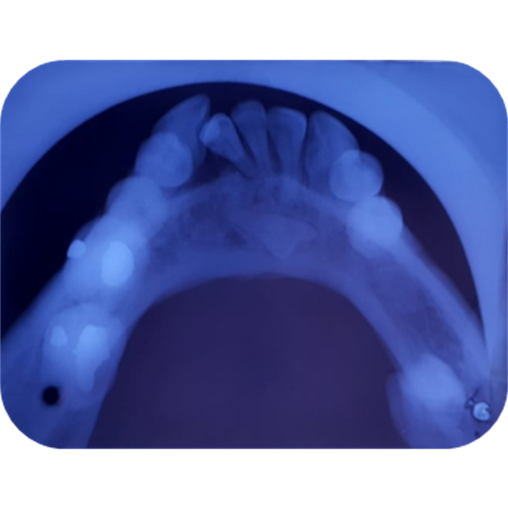

Imagen 1. Fotografías intraorales

El estudio radiográfico puede evidenciar múltiples sombras radiopacas rodeadas de un halo radiolúcido pertenecientes a un tumor odontogénico CIE10: D164 (odontoma compuesto), localizados en a nivel de los órganos dentarios 4.3; 4.1; 3.1; 3.2; 3.3. También se puede constatar la presencia de una sombra radiopaca que concuerdan con el órgano dentario retenido.

Imagen 4. Oclusal Inferior.

El diagnóstico y tratamiento oportuno que se debe tener frente a las neoplasias odontogénicas que son frecuentes en la consulta odontológica, y la mayoría de casos pasa desapercibido nos hacen tomar conciencia de lo importante de tratar , guiar a los pacientes que visitan la unidad de atención odontológica Uniandes a realizarse exámenes complementarios, radiográficos panorámicos, periapicales, oclusales que tienen la posibilidad de demostrar una visión más clara de las estructuras dentarias vecinas, previniendo desarrollos o formaciones de neoplasias ya que, las radiografías las intraorales periapicales, oclusales demuestra mayor fidelidad dimensional en comparación a la panorámica detectando oportunamente patologías que son asintomáticas.

En su gran mayoría en la presentación de este caso clínico se puede observar la presencia de una sombra radiopaca que concuerdan con el órgano dentario retenido 4.2.con una imagen mixta con múltiples radiopacidades muy similares a los órganos dentarios que están rodeados de un halo radiolúcido perimetral que son similares descripciones de investigaciones de otros autores.